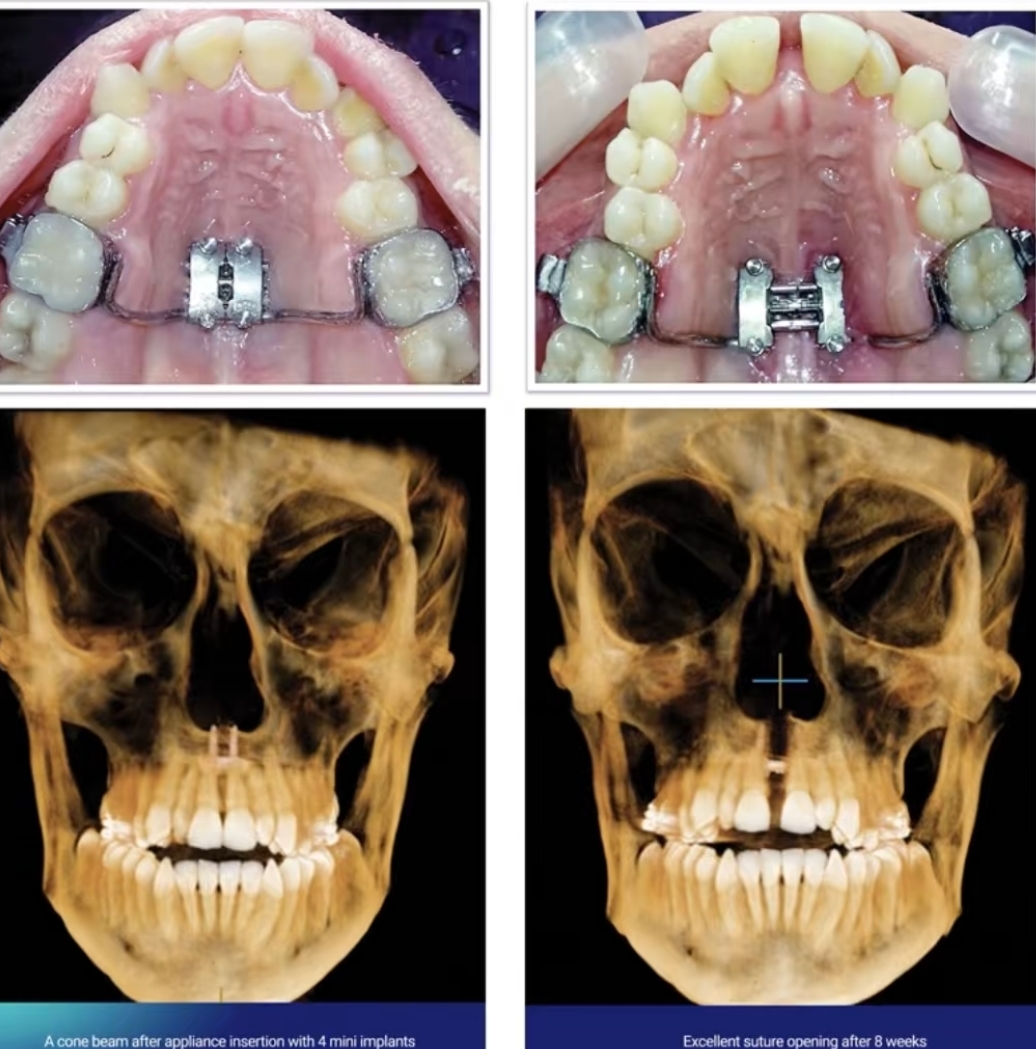

Orthodontics, mse or damon braces to widen ur maxilla. But it has to be recessed to get it in the first place. No exercises or pullings work. Theyre all cope

This is expantion to your pallet